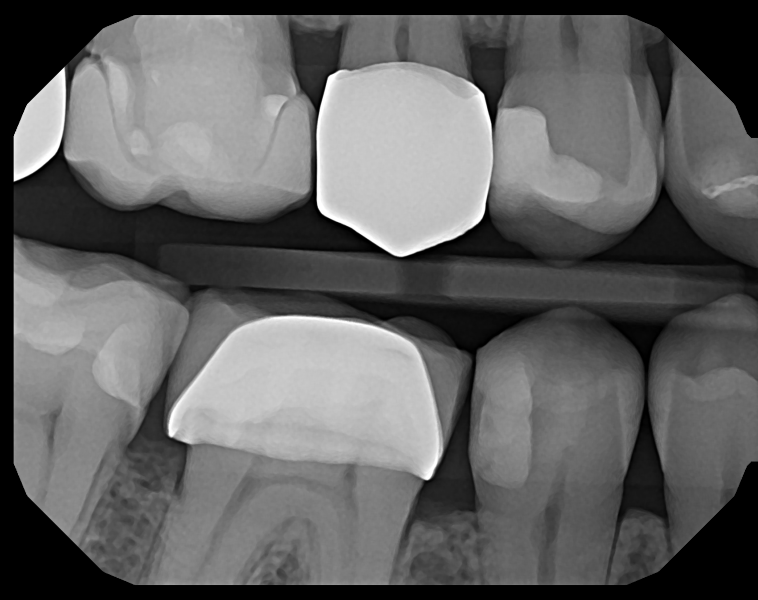

Crisp Images, Low Exposure

The low-noise design delivers exceptional clarity even at lower doses. Keeps patients safer while improving diagnostic confidence.

Capture Every Detail — High-Quality Imaging. Designed for Patient Comfort.

See The Clarity For Yourself

• Left Bitewing

• Mandibular Anterior

• Right Bitewing

• Maxillary Anterior